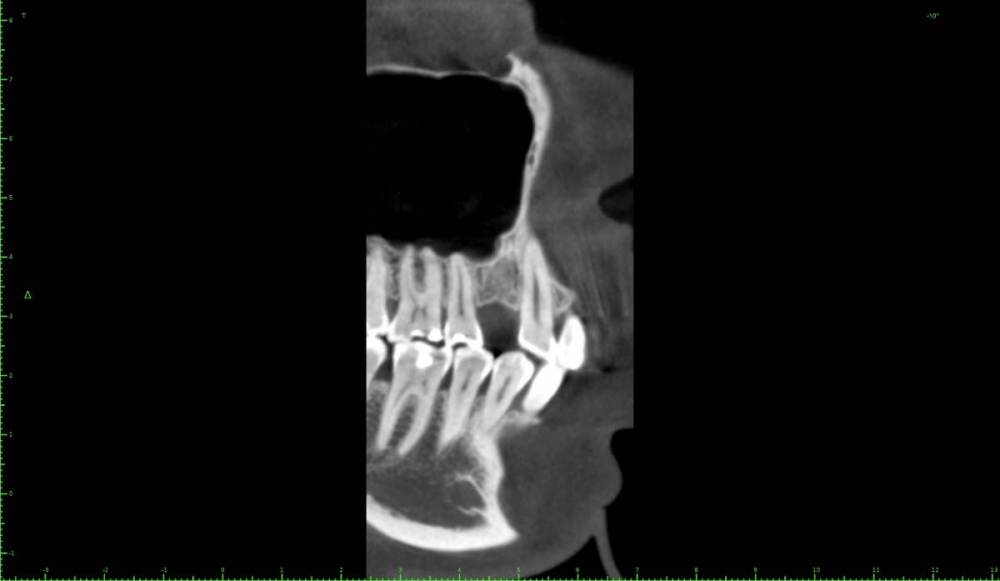

Женька Опубликовано 1 апреля, 2021 Поделиться Опубликовано 1 апреля, 2021 Значит придётся пациентке отказать... Не понимаю пока куда тут можно зслить и как. Про бш помню-знаю. Но топить нужно же не в кости 3-4 мм? Ссылка на комментарий

It'sGeorgy Опубликовано 13 апреля, 2021 Поделиться Опубликовано 13 апреля, 2021 Добрый день. Какие особенности будут при удалении подобного зуба? Какова вероятность анкилоза или это здесь вообще не при чем? Ссылка на комментарий

red_butler Опубликовано 13 апреля, 2021 Поделиться Опубликовано 13 апреля, 2021 15 минут назад, It'sGeorgy сказал: Какие особенности будут при удалении подобного зуба? перфорация и возможно миграция зуба в синус 2 Ссылка на комментарий

It'sGeorgy Опубликовано 13 апреля, 2021 Поделиться Опубликовано 13 апреля, 2021 6 минут назад, red_butler сказал: перфорация и возможно миграция зуба в синус Спасибо, это само собой. Меня интересует затемнение на зубе, влияет ли оно на что-то? Ссылка на комментарий

red_butler Опубликовано 13 апреля, 2021 Поделиться Опубликовано 13 апреля, 2021 8 минут назад, It'sGeorgy сказал: Меня интересует затемнение на зубе, влияет ли оно на что-то? похоже на внутреннюю резорбцию, не вижу с ней проблем 1 Ссылка на комментарий

Женька Опубликовано 1 мая, 2021 Поделиться Опубликовано 1 мая, 2021 01.04.2021 в 13:26, red_butler сказал: заглубить с проведением ЗСЛ у все пройдет Ну что же. Пациентка согласилась на синус и имплантацию...а я надеялся что нет Только планирую пойти через открытый все-таки. Тк во-первых это можно сказать первый синус, во-вторых боюсь что при зсл я получу перфо ввиду анатомии синуса. Ссылка на комментарий

Irouil Опубликовано 1 мая, 2021 Поделиться Опубликовано 1 мая, 2021 (изменено) Вы тут с открытым синусом в 10 раз вероятнее накосячите, чем с закрытым Потому что даже если просто перфорнуть тут пазуху при ЗСЛ с очень высокой долей вероятности произойдёт чуть менее чем ничего А если начать отслаивать слизистую пазухи отдельным доступом, да еще и прямо по медиальной границе альвеолярной бухты, да еще и так высоко, да еще и планировать натолкать туда графта или еще какой-нибудь дряни... сразу ЛОРа хорошего номер ищите) Изменено 1 мая, 2021 пользователем Irouil 2 1 Ссылка на комментарий

Женька Опубликовано 2 мая, 2021 Поделиться Опубликовано 2 мая, 2021 А я думал наоборот. Открытый проще во всех смыслах Предлагаете просто зсл, губку если перфо внутрь, если нет то просто поднять пазуху и всё? без графтов чисто на сгустке? Ссылка на комментарий

Irouil Опубликовано 2 мая, 2021 Поделиться Опубликовано 2 мая, 2021 Без графтов, преп на -1-1.5 мм от высоты гребня пилотном, потом конденсация до 3.2 (или какой там у Вас диаметр вогнутого остеотома), дальше стук, по необходимости конденсинг и профайлинг крестального модуля либо реверс-препинг всей длины (в зависимости от планируемого винта) потом просто крутить 8 мм в этой ситуации на мой взгляд ничем графтить не нужно Ссылка на комментарий